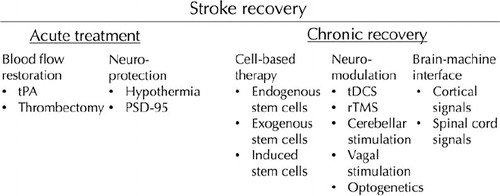

What is going on here? I'll be presenting our PET work at 5.30pm, MP 29. Why not come and find out more? #ISC2017 @DunhillMedical @CamStroke